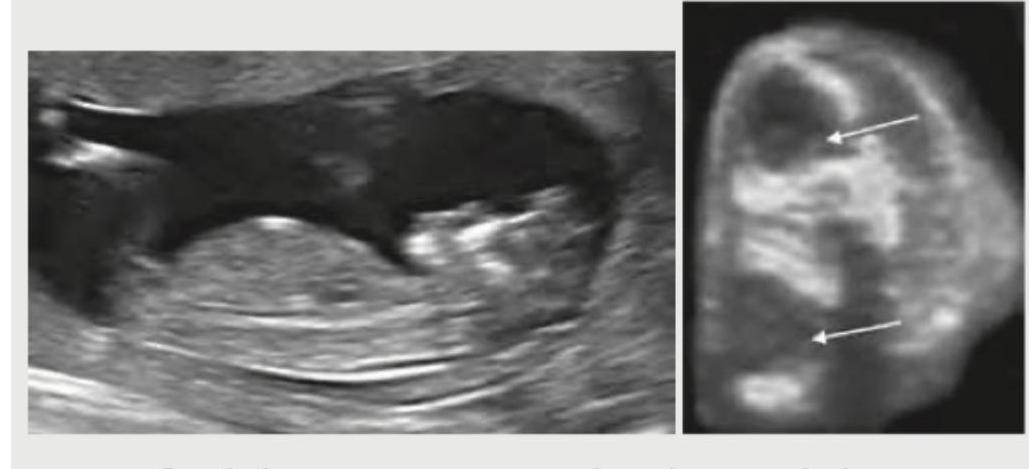

A 21-year-old G2P1 presents to OPD at 20 weeks of gestation for a second opinion since her family physician had told her that the foetus had some problem. Her obstetric USG is given below. What is the diagnosis? (AIIMS May 2016)

Explanation: ***Anencephaly*** - The ultrasound images clearly show the **absence of the cranial vault** and the **cerebral hemispheres**, which is characteristic of anencephaly. The upper arrow in the right image points to the irregular brain tissue that is exposed, not covered by bone. - The "frog-like" appearance of the fetal head, with exposed brain tissue, is a classic sonographic finding for this neural tube defect. *Cystic hygroma* - A cystic hygroma would appear as a **multiloculated cystic mass**, typically in the posterior neck region, often associated with chromosomal abnormalities. - The image does not show such a cystic mass; instead, it shows a defect in the fetal skull. *Omphalocele* - An omphalocele involves the **protrusion of abdominal organs** into the umbilical cord base, covered by a membrane. - This condition affects the abdominal wall, not the fetal head or brain, and would appear as an abdominal mass rather than a cranial defect. *Encephalocele* - Encephalocele is characterized by the **protrusion of brain tissue and/or meninges** through a defect in the skull, typically covered by skin or a membrane. - In encephalocele, while some brain tissue might protrude, the **cranial vault is still visible**, unlike the complete absence seen in anencephaly.